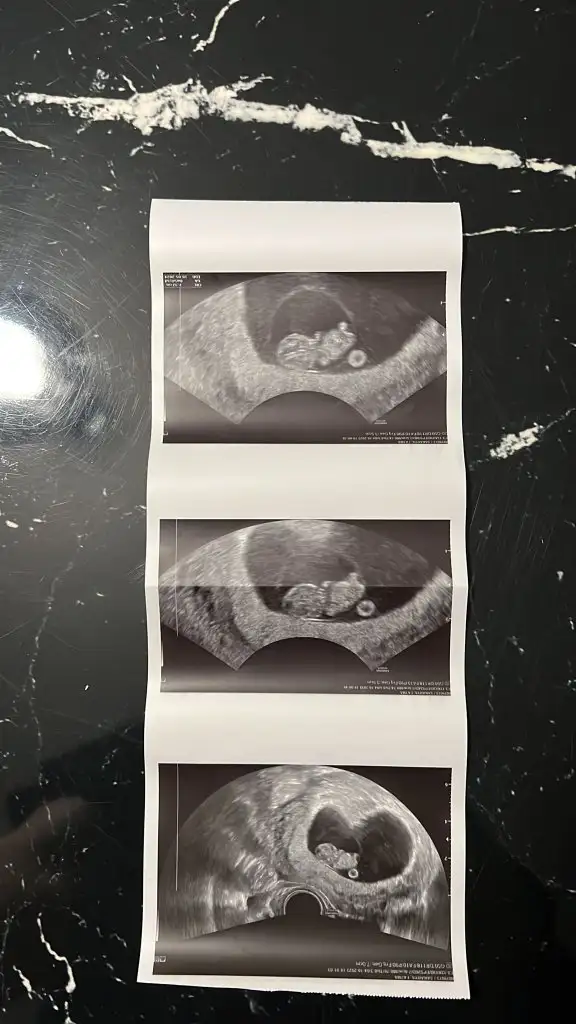

dr soylemeden siz gorun genital nub teorisi ( bebegin cinsiyeti)

Merhaba benşm içinde tahminde bulunurmusunuz 🫶 8 haftalık karından usg